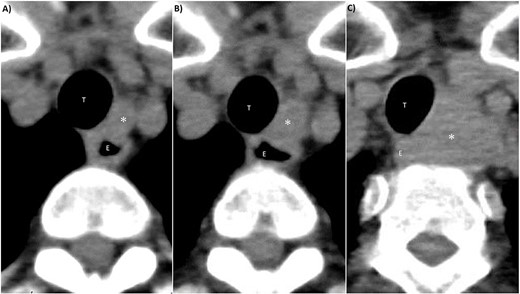

A 70-year-old female without any past medical history underwent total thyroidectomy and central neck dissection for PTC (pT3bN1aM0 pStage II; Fig. 1). Pre-operative blood examination showed a thyroglobulin (Tg) level of 351 ng/mL (normal value of Tg, ≤33.7 ng/mL). After surgery, her Tg level remained around 100 ng/mL (Fig. 2). However, 5 years after initial surgery, her Tg level increased to 366 ng/mL, with subsequent computed tomography (CT) revealing metastasis to the left III (Fig. 3) and right Vb and VI lymph nodes. CT also incidentally observed a right ovarian tumor, for which transvaginal ultrasonography and magnetic resonance imaging (MRI) were performed given suspicions of malignancy (Fig. 4). Blood examination showed a CA125 level of 33.4 U/mL (normal value of CA125, ≤35.0 U/ml). Given suspicions of malignancy by our hospital’s department of gynecology, total hysterectomy and bilateral adnexal resection had been conducted. A pathological diagnosis of OG with no malignancy was then established (Fig. 5). The patient’s post-operative Tg level decreased to 143 ng/mL (Fig. 2). For lymph node metastasis of PTC, right neck dissection and left III lymph node resection by sternal incision were performed. The left recurrent laryngeal nerve was resected due to the invasion of the left III lymph node. Though post-operative swallowing rehabilitation was needed, she was discharged 9 days after surgery with good clinical course. Post-operative blood examination showed a significant decrease in the Tg level (5.9 ng/mL).

CT findings of left III lymph node metastasis. (A) 4 years after initial surgery, size: 9 mm × 7 mm. (B) 5 years after initial surgery, size: 14 mm × 10 mm. (C) 7 years after initial surgery, size: 32 mm × 27 mm. *: left III lymph node, T: trachea, E: esophagus.